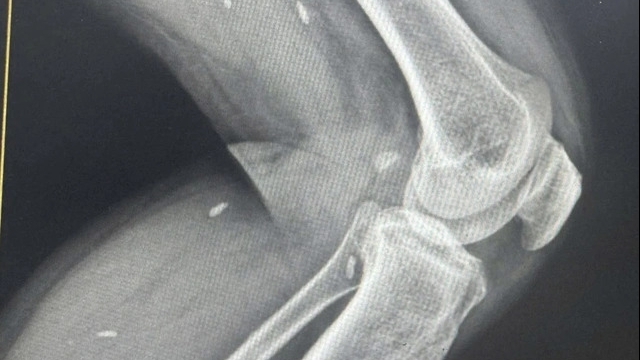

Tại đây, T được các bác sĩ tiến hành thăm khám, chụp cắt lớp vi tính thấy có dị vật trong ổ bụng kích thước 3cm và bụng nhiều dịch mủ.

Bệnh nhân nuốt phải tăm vào bụng mà không hay biết. Que tăm nằm trong bụng suốt một tuần đâm thủng ruột và gây nhiễm trùng ổ bụng nặng.

Người bệnh nhanh chóng được các bác sĩ phẫu thuật cấp cứu bằng phương pháp phẫu thuật nội soi kết hợp với mổ mở, lấy ra một dị vật dài 3cm nhọn 2 đầu bằng tre, khâu lại lỗ thủng ruột, rửa sạch mủ và dịch tiêu hoá trong ổ bụng. Hiện tại sau mổ tình trạng của người bệnh tạm thời ổn định.